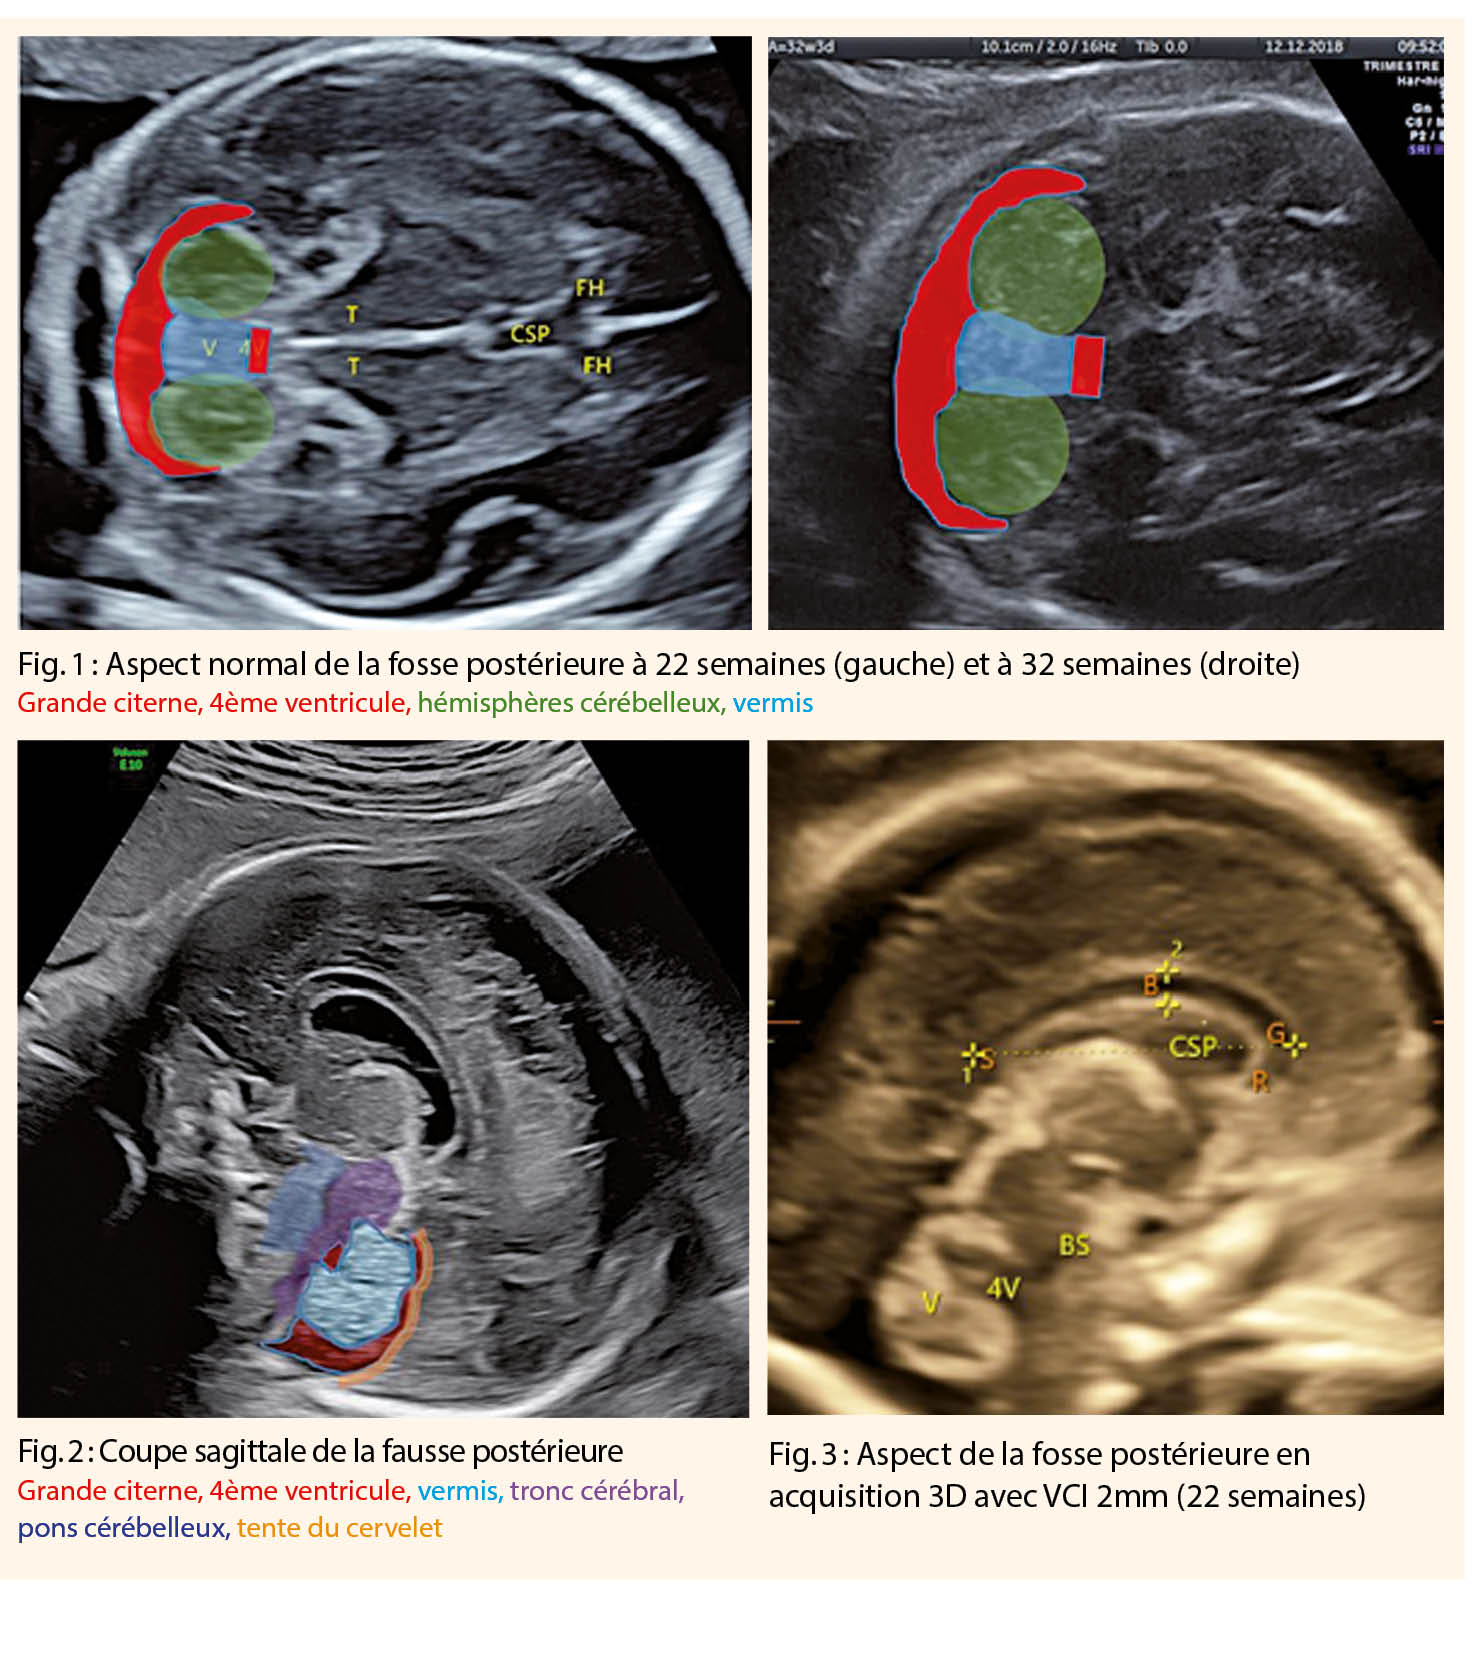

En partant d’ une coupe axiale trans-thalamique, coupe du « Bip », la partie de la sonde orientée vers l’ occiput du fœtus est abaissée afin de visualiser le cervelet (fig. 1).

• Anatomie du cervelet : le vermis est entouré de deux hémisphères cérébelleux symétriques, séparant le 4ème ventricule en avant et la grande citerne en arrière

Cette coupe peut être réalisée au travers de la suture sagittale ou de la fontanelle postérieure par un abord trans-abdominal (fœtus en siège ou en présentation transverse) ou trans-vaginal (fœtus en présentation céphalique) (fig. 2) (2, 6).

L’ acquisition 3D de la fosse postérieure peut-être réalisée à partir d’ une coupe axiale trans-cérébelleuse (Figure 1).

A partir du mode triplan, la ligne inter-hémisphérique sera placée de manière orthogonale afin d’ obtenir une coupe sagittale du vermis (fig. 3).